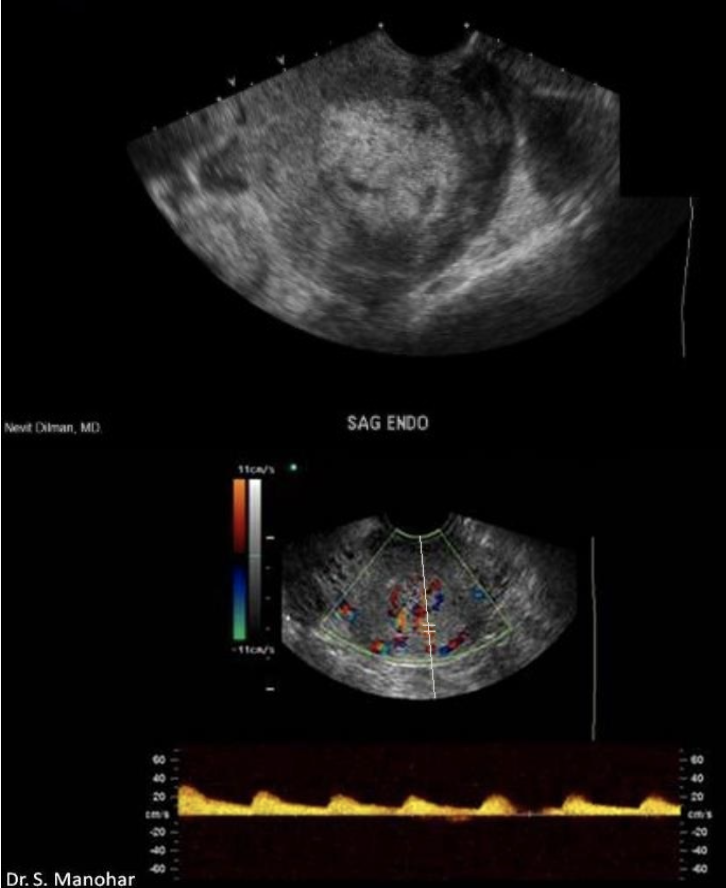

an abn of renal fusion where the lower pole of kidneys are connected across the midline of abd called

a) horseshoe kidney

b) epispadias

c) cross fused renal ectopia

d) persistent cloaca

what congenital anomaly is shown

a) renal agenesis

b) duodenal atresia

c) anal atresia

d) posterior urethral valves